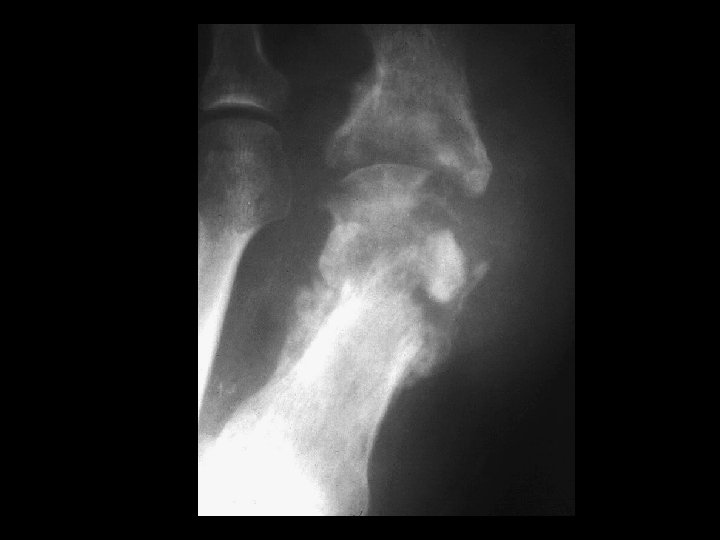

Septic Arthritis • Findings: – Lytic and sclerotic destruction of the great toe MTP joint – Joint space narrowing – Periosteal reaction – Soft tissue swelling • ddx: – Charcot joint – Metastasis with pathologic fractures